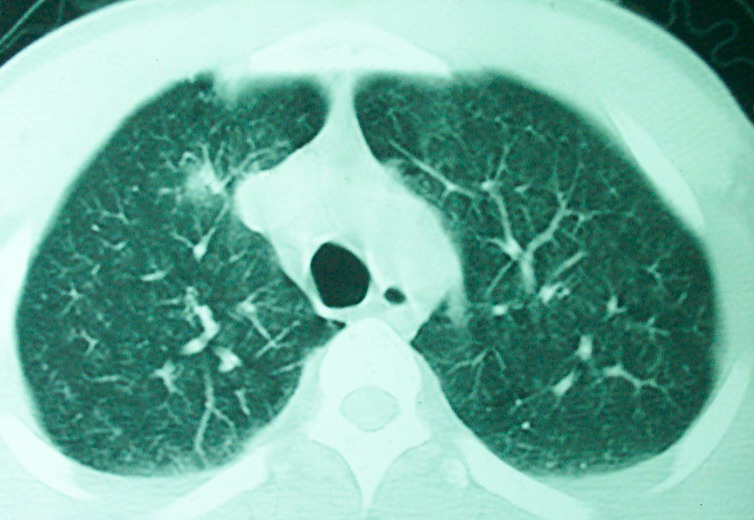

m      37y      发热   咳脓痰月余      ct肺脓肿但住院抗炎治疗后双肺内结节不知该如何解释

治疗后见左肺下野病灶较前缩小但双肺内结节影似无变化请较各位老师该如何下结论    治疗前wbc14.5 治疗后wbc 11.0

如果你仔细的同层面对比,你会发现所有的病灶均有比较明显的吸收、缩小。病变的形态,特别是脓肿的形态、壁的厚薄、内壁均有很大的变化,均在往好的方面发展。与临床症状、血像均符合,治疗效果比较显著,就是肺脓肿并双肺的化脓性炎症灶。